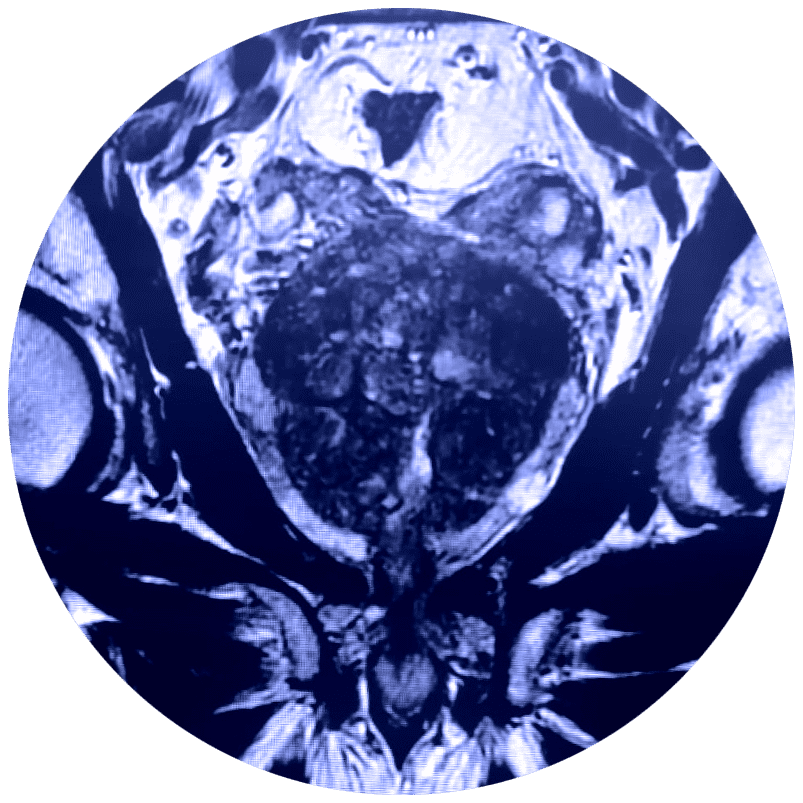

El estudio de Resonancia Multiparamétrica de Próstata no requiere de exposición a la radiación, evalúa el movimiento de las moléculas de agua (denominado difusión del agua) y el flujo sanguíneo (denominado imágenes de perfusión) adentro de la próstata. Esto ayuda al médico a diferenciar entre el tejido enfermo y el tejido sano de la próstata.

En estudio de Resonancia Multiparamétrica de Próstata tiene una sensibilidad diagnóstica de aproximadamente el 85% en los diferentes tipos de cáncer de próstata, especialmente aquellos que son significativamente agresivos. Además, cuenta con imágenes de alta resolución para lesiones o tumores pequeños.

Respecto al cáncer de próstata la Resonancia Magnética Multiparamétrica ha adquirido en los últimos años un papel importante, tanto en el diagnóstico en caso de elevación del PSA (antígeno prostático específico en sangre) con biopsias negativas, como en la estadificación local y a distancia, e incluso en la monitorización del tratamiento.

El médico utiliza la RMN para evaluar el cáncer de próstata y ver si se encuentra confinado a la próstata. La Mp-MRI proporciona información acerca de las moléculas de agua y del flujo sanguíneo a través de la próstata. Esto ayuda a determinar si el cáncer se encuentra presente y, si es el caso, si es agresivo y si se ha diseminado.